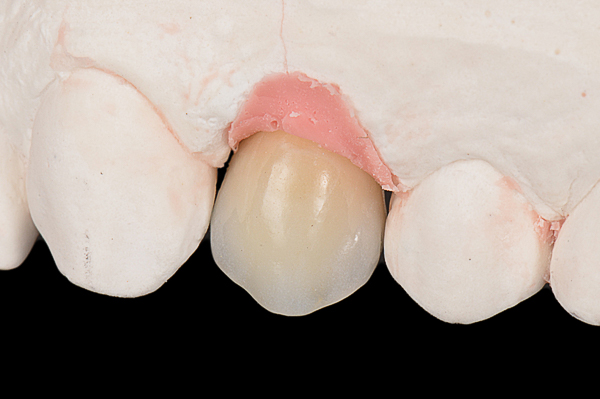

A seguito dell'analisi radiografica viene pianificata l'estrazione atraumatica del premolare con l'inserimento contestuale di un impianto Shelta. La riabilitazione immediata viene eseguita con un pilastro XA per protesi avvitata, su cui viene fissato un provvisorio realizzato in laboratorio secondo i principi dei profili di emergenza della tecnica B.O.P.T.

Donna, 37 anni, non fumatrice, con una buona igiene, si presenta in studio con un fallimento del trattamento endodontico dell'elemento 1.4.